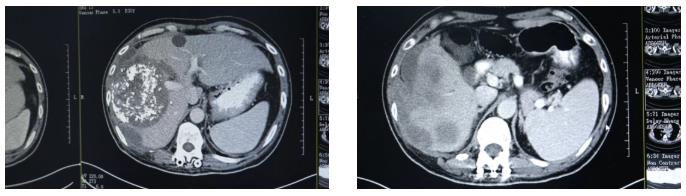

在当地医院,勇哥接受了一次介入灌注化疗栓塞术,但反应剧烈,“反复发烧,烧了足足半个月”。好不容易烧退了,复查结果却更令人绝望:肝脏病灶扩大到13.2厘米,肺转移瘤增多,肝门区、腹腔淋巴结密密麻麻。医生跟他说肿瘤扩散太广,无法手术,最多只剩“两个月时间”。

第三次回院复查时,勇哥的甲胎蛋白已降至800多,CT显示肝癌及肝内多发转移瘤、双肺转移瘤及大网膜转移瘤都较前缩小,无新发病灶,病情评价为稳定(SD)。“这次做介入治疗时,医生告诉我肝上肿瘤基本没有活性了。”勇哥的声音中带着久违的轻松。